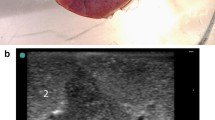

Human lung lobes from surgery were used for this study. The ex-vivo lung model generates the same quality of gas free lung parenchyma as in-vivo models and is described detailed elsewhere [6]. The samples were resected under curative intent treatment from lung cancer patients. Immediately after resection, flooding was performed with tempered (35 °C), degassed saline (0,9%) until a static pressure of 20 cm water column was achieved. The flooding was qualified by sonography using a portable imaging system (Sonosite Inc., Bothell, WA, USA) with high frequency linear probes (Fig. 1). In total, seven flooded human lung lobes (47–73y, mean 61y) were used (3 upper, 1 middle, 3 lower) in this study.